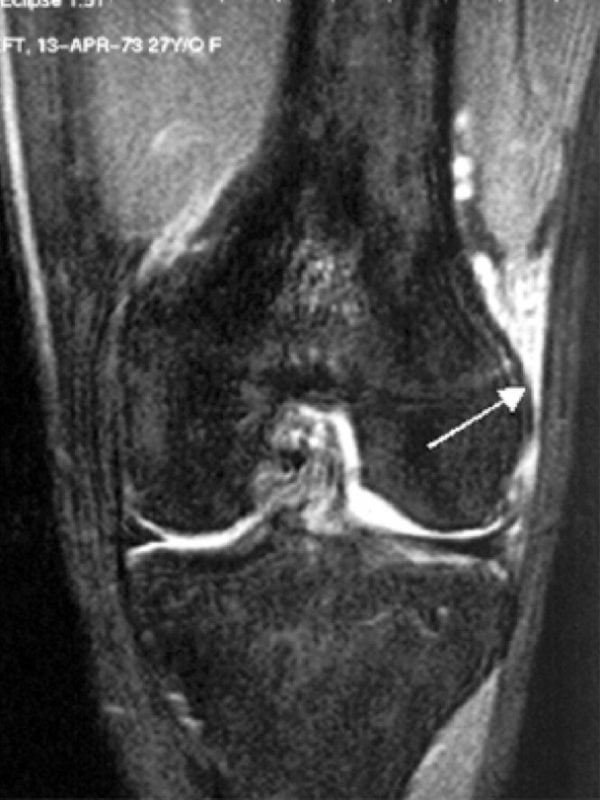

A síndrome da banda iliotibial (SBIT) é a causa mais comum de dor na região lateral dos joelhos em corredores. Corredores predispostos a essa lesão geralmente encontram-se em fase de sobretreinamento e muitas vezes apresentam fraqueza subjacente ao músculo abdutor do quadril. Corredores homens podem exibir falhas cinemáticas, como.

Sintomas. O principal sintoma da síndrome é dor na lateral do joelho, apresentando piora após exercícios físicos. Outros sintomas incluem: Hipersensibilidade na extremidade distal e lateral do fêmur (próximo ao joelho); Dor em queimação durante a palpação; Em casos mais avançados, dor na região lateral da perna.

A síndrome da banda iliotibial causa dor na parte externa do joelho devido ao uso excessivo. A síndrome da banda IT é mais comum em atletas de resistência, como ciclistas e corredores.. Os sintomas desenvolvem-se lentamente e muitas vezes não há história de lesão. Principais sintomas. Dor profunda ao longo do lado externo do joelho.